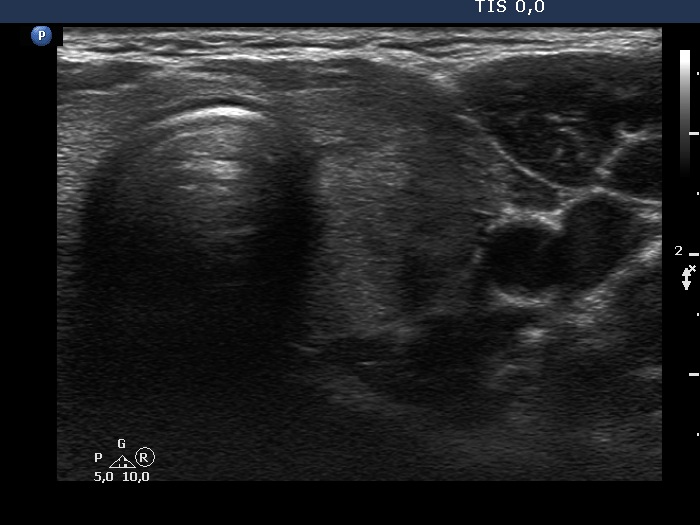

Four months after the previous examination (third row of images):

Clinical presentation: The neck complaints and elevated body temperature have immediately ceased and did not recur.

Palpation: no abnormality.

Laboratory tests: TSH 1.14 mIU/L, FT4 12.2 pM/L, CRP 0.49 mg/L, aTPO 0.6 U/mL.

Ultrasonography: The extent of hypoechoic areas has decreased. The left lobe became significantly smaller. The vascularity remained scanty.

Suggestion. Follow-up in six months.

Comment. This is a very rare situation that we examine a patient long before the onset of a subacute thyroiditis and therefore we can prove that her thyroid was healthy.